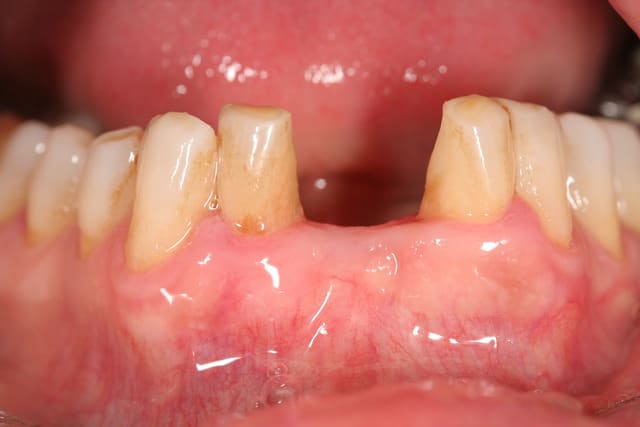

et ici ?? vous feriez quoi ?

32 et 42 pas mobiles

malheureusement, l'espace est réduit pour mettre deux implants.

comment avez vous déjà géré ce type de cas ??

le haut est déjà traité...

à propos du cas , j'ai vu avec la patiente cet aprem; nous avons décidé de faire un petit bridge provisoire de quelques mois et si (après traitement paro bien sure) les dents ne sont pas mobiles, on passera au bridge définitif. sinon, ce sera pose de deux implants en position 42-32 pour éviter une greffe que la patiente refuse.